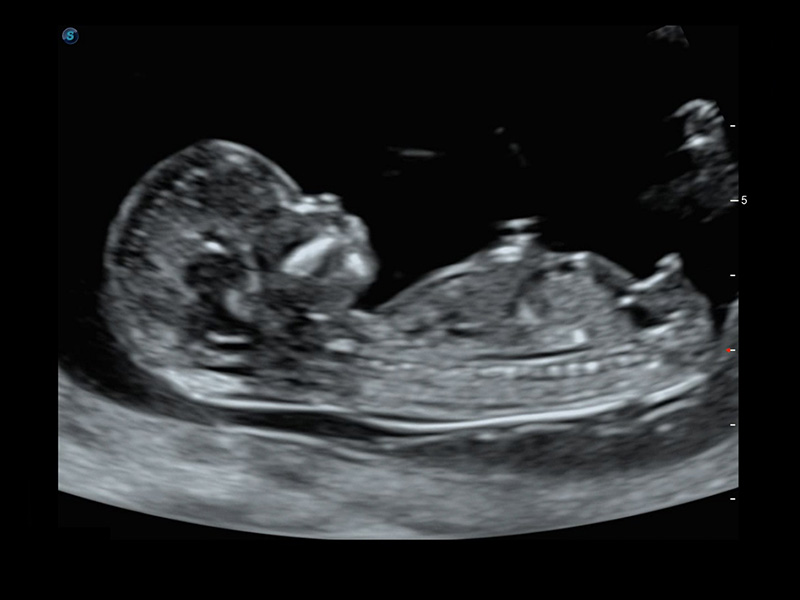

S-Fetus*

S-Fetus è uno strumento di facile utilizzo che consente il rilevamento completamente automatico e preciso dei piani più significativi e delle misurazioni della biometria fetale, utilizzate frequentemente. Con la modalità cine-loop della testa del feto, S-Fetus è in grado di estrarre i piani standard e visualizzare i risultati della misurazione in un secondo, riducendo notevolmente Il numero di battute e i tempi di lavoro necessari. È progettato per trasformare gli esami ecografici ostetrici in un'esperienza molto più comoda, veloce e piacevole.

1 OFD(HC): 87,03 mm

HC: 251,00 mm

GA: 27w 1d

HC/AC: 96,13%

2 BPD: 70,56 mm

GA: 28 w 2d

S-Fetus(acq.)

& S-Fetus(meas.)